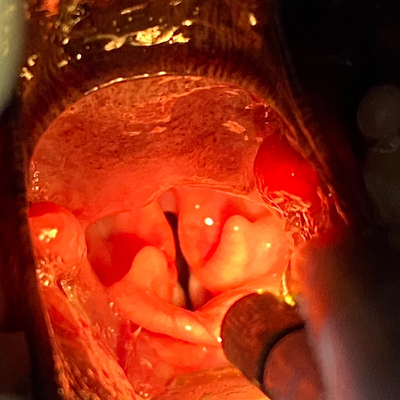

내시경 검사로 후두부를 확인했어요. 눈으로 확인하기 어려운 작은 변화도 내시경 검사를 통해 자세히 조사할 수 있었습니다.

◆ 후두부 확인

후두부를 검사할 때는 연골의 크기 차이밖에 문제가 되지 않았습니다. 그래서 후두부에서 구강을 향해 천천히 내시경을 채취하면서 검사를 해 보았습니다.

◆ 편도선염과 부종

양쪽 편도선이 부어있는 것 같았어요 특히 왼쪽 편도선은 출혈까지 확인되었는데

◆ 내시경 동영상

개가 콧물과 코 막힘의 증상과 킁킁 소리를 내며 내시경으로 후두부를 검사했습니다. 검사 결과 편도선 염증이 확인되었습니다.